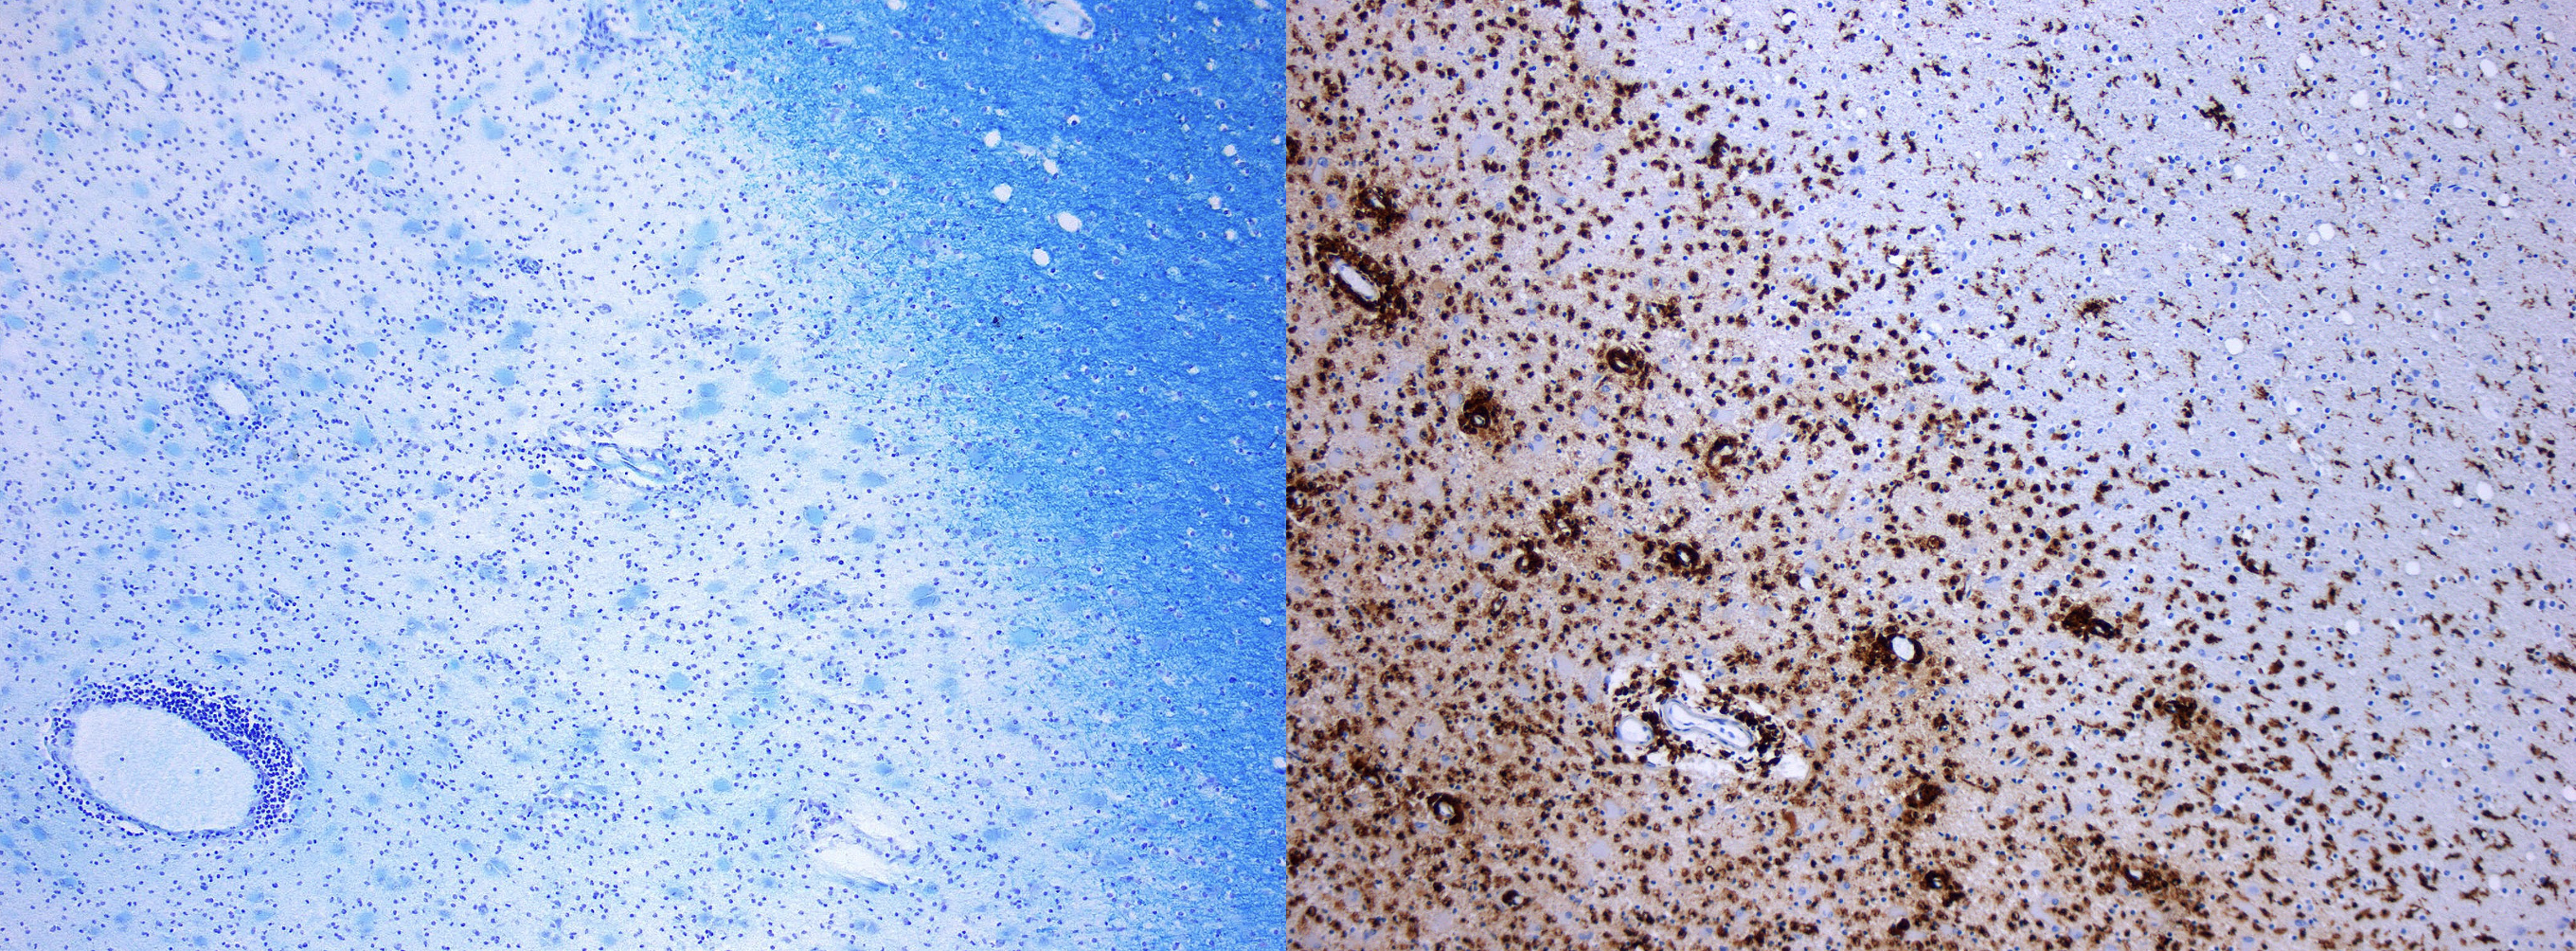

MS lesions can be designated as active, inactive, or mixed active/inactive. This differentiation is based on the distribution of inflammatory cells around the plaque and the existence of demyelination. Histological and immunohistological stains can be used for identifying these lesions. For example, myelin can be seen with special stains (e.g. Luxol fast blue, Klüver-Barerra-Stains) while cell morphology can be seen with hematoxylin and eosin stains. Moreover, inflammatory cells such as macrophages can be seen with immunohistochemical markers (e.g. CD68). Thus, a combination of the prementioned stains can help illuminate the loss of myelin in neurons caused by macrophages.

Figure 12-53. Histologic staining of MS lesion showing loss of myelin staining (left) and increase in macrophage staining (right). The picture on the left shows brain tissue stained with Klüver-Barerra, which colours myelinated tissue a bright navy blue. The area of discolouration indicates demyelinated MS plaque tissue. The picture on the right shows immunohistochemical staining for CD68, in which the brown dots indicate the presence of macrophages. This image shows that there are many more macrophages within the lesion compared to the normal tissue.

https://commons.wikimedia.org/wiki/File:MS_Demyelinisation_KB_10x.jpg

https://commons.wikimedia.org/wiki/File:MS_Demyelinisation_CD68_10xv2.jpg

It should be noted that the presence of inflammatory cells within the plaques varies depending on the lesion’s stage. While active lesions tend to contain many macrophages, inactive/chronic lesions often contain few or none. Thus, stains such as CD68 may help determine lesion stage.